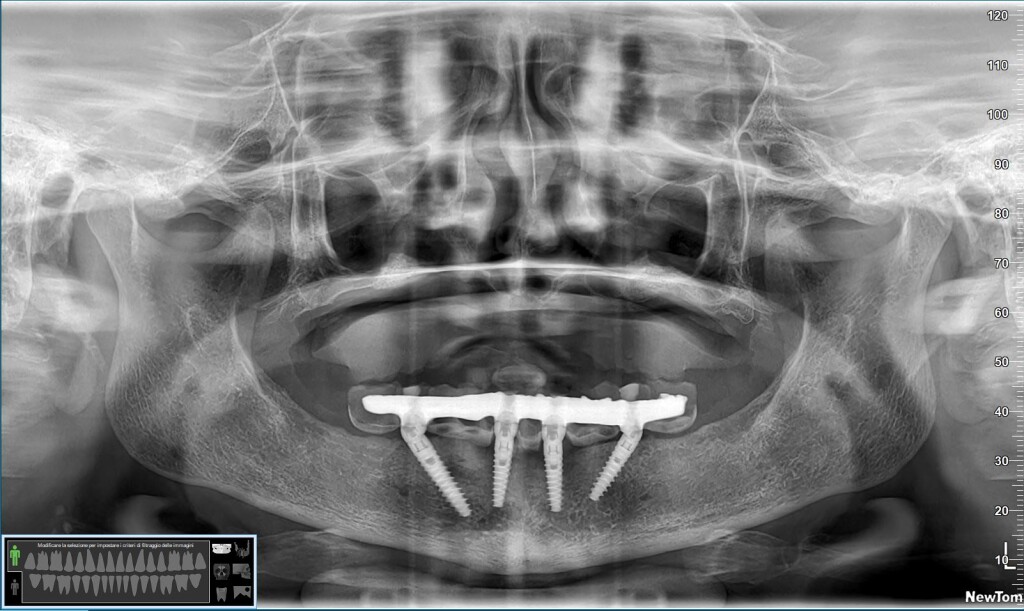

La paziente era stata trattata circa quattro anni fa presso un centro low cost del centro Italia, e quello che è successo a livello chirurgico è abbastanza chiaro: l’inconsapevole “chirurgo” aveva posizionato gli impianti in osso alveolare nella vana speranza che questo si preservasse nel tempo.

Stupidaggine, tra l’altro, che sta tornando in grande voga negli ultimi anni e che, come già avvenuto vent’anni fa, si riverserà sulle teste di chi la propina con una marea di fallimenti come quello che vedi qui.

Come si può osservare dal video, gli impianti non sono in perimplantite: semplicemente, l’osso si è riassorbito attorno lasciandoli fuori.

Concetto ovvio per chiunque conosca la biologia, ma non tanto per chi si fa progettare le mascherine della guidata dal rappresentante di certe case implantari! 🙄